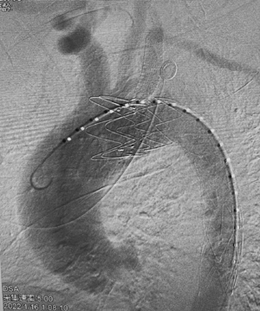

午夜十二点,手术开始,由血管外科贾伟、蒋鹏、程志远三位高年资大夫组成手术团队。介入下,清楚看到患者主动脉破口紧邻左侧锁骨下动脉,如果按照常规手术方案治疗虽然可以挽救病人生命,但必然导致左侧锁骨下动脉闭塞而使左上肢缺血,术中贾伟副主任医师当机立断,决定采用非常规的手术方案:原位体外开窗、保留左锁骨下动脉。虽然手术难度增加了数倍,但是左锁骨下动脉的血流成功保留对病人的意义重大。手术耗时1个多小时顺利结束,凌晨一点半病人转入ICU病房,目前各项生命体征平稳。